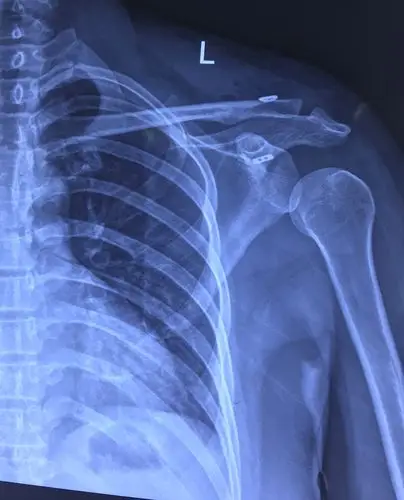

肩锁关节脱位

左肩锁关节脱位